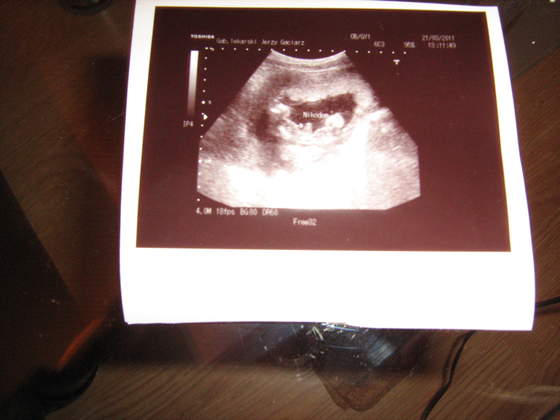

Jutro mam 4d, jak potwierdzi mój arabski spec chłopaka to Wam wstawię zdjęcie siusiaka ;-)